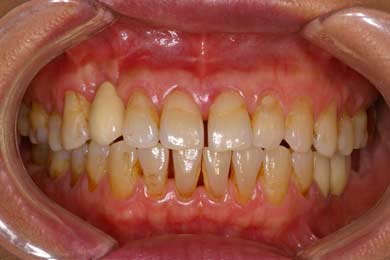

주된 원인은 치태와 치석이다. 흔히 ‘플라그’라고 부르는 치태는 입안의 음식물 찌꺼기와 세균이 모여 치아 표면에 형성된 것이다. 치태는 시간이 흐를수록 딱딱해져 칫솔질로도 제거되지 않는 치석으로 변한다.

이런 치태와 치석이 잇몸 안쪽으로 파고들면 염증이 생길뿐더러 그 증상이 치주인대와 치조골까지 파급되는 양상을 보이다 급기야 치아가 빠지기도 한다. 당뇨나 영양부족 같은 전신질환이나 흡연, 스트레스, 유적적인 요소들이 부가적으로 작용하게 되면 증상이 더욱 악화된다.

강북구 에스다인치과(S다인치과) 강성용 원장은 “나이가 들수록 침의 분비가 감소하고, 치아도 수분이줄어 깨지기 쉬우며 치아의 마모도 많이 진행된다. 잇몸이 줄어들면서 치근도 노출되기 때문에 풍치의 발생 및 악화 가능성이 높고 이에 따른 치아 상실의 위험이 매우 커진다”고 전했다.

풍치의 문제점은 초기에 증세가 거의 나타나지 않는다는 것. 치아뿌리를 감싸고 있는 치조골이 절반쯤 녹아내려야 약간의 자각 증상이 나타난다. 이때 병원을 찾더라도 이미 잇몸이 상당히 상한 상태여서 풍치의 진행을 막아주는 치료만 할 수 있을 뿐이다. 때문에 잇몸질환이 없어도 6개월에 한번 정도 치과를 방문해 검사를 받는 것이 좋다.

에스다인치과 강성용 원장은 “염증이 잇몸에만 국한돼 있는 초기라면 스케일링만 받아도 완치가 가능하지만 증세가 심한 경우 국소 마취 후 부어오른 잇몸을 잘라내고 치아 뿌리 깊숙이 박힌 치석과 불순물을 제거해야 한다”고 말했다. kubee08@kukimedia.co.kr